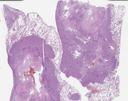

病理切片

SLIDE